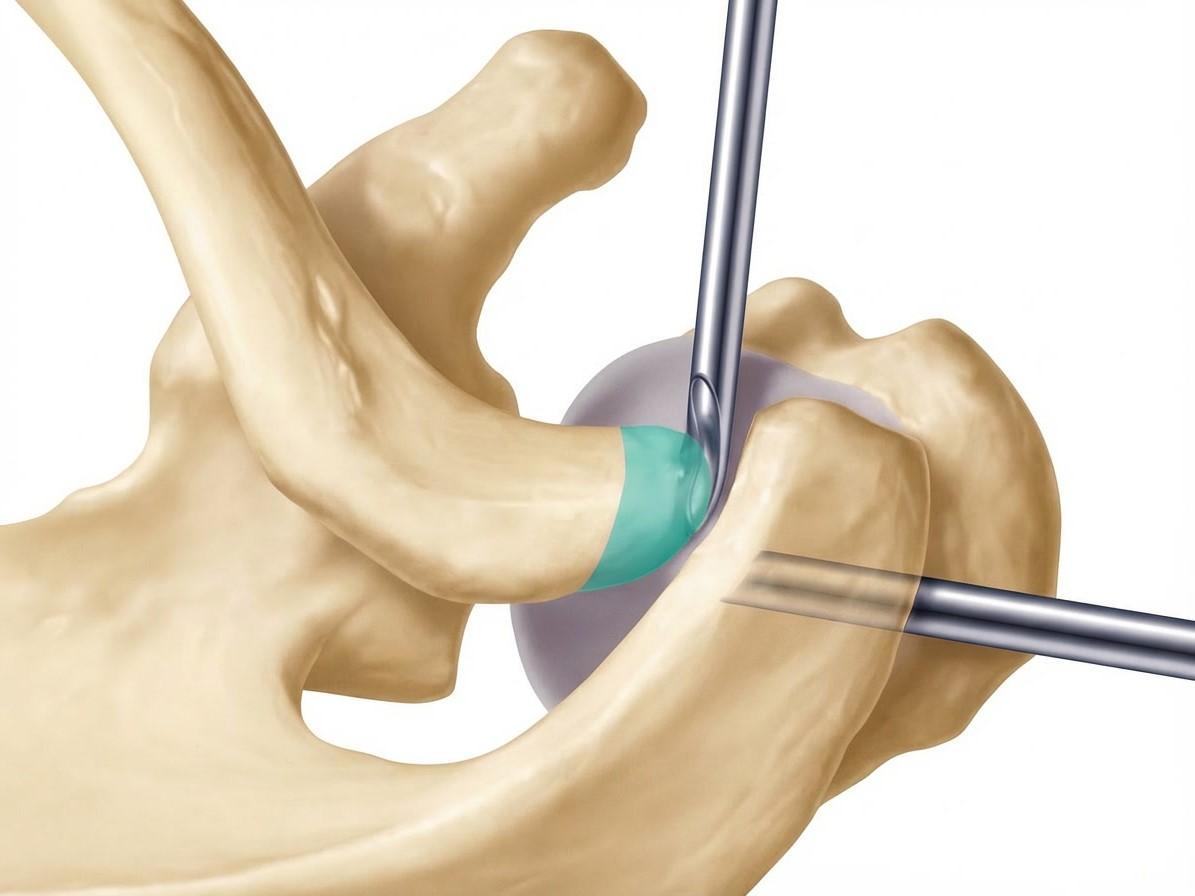

Abtragen der lateralen Clavikula

• Abtragung von ca. 5-10 mm des lateralen Klavikulaendes

• Instrumente:  motorisierte Shaver

• Kontrolle: ausreichender Spalt ohne Knochenkontakt bei Bewegung